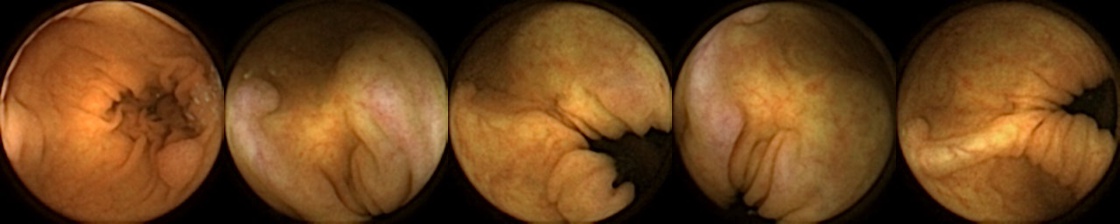

Similarly, we consider examples for the MIV model based on SimCLR pretraining using the pretrained ConvNext backbone in Figure 4. The model has a test accuracy of 86.26% for DBA L1 with 2 heads. Here we note again a similar trend by looking at the True Positive and False Negative examples as observed before, where a significant difference in the query image when compared with the target images can lead to a failure to identify the same polyp images in the five examples. A look at the False Positive examples affirms that the task remains challenging, as evidenced by the model’s occasional misclassifications in ambiguous cases.

True Positive False Negative

False Positive True Negative

Figure 4: True Positives (Pred = true, Label = true), False Negatives (Pred = false, Label = true), False Positives (Pred = true, Label = false),True Negatives (Pred = false, Label = false) for the DBA L1(h=2) model applying SimCLR using the ConvNeXt backbone. In each row, the leftmost image is the query and the 4 images to the right of each query are the target images.